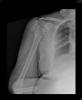

Fractura impactada de húmero .

Fractura de húmero, intensa desviación de fragmentos